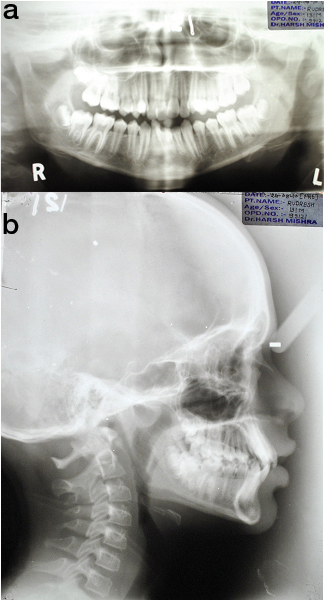

A 13-year-old, male patient presented with a chief complaint of irregularly placed upper front teeth. He was diagnosed as a case of skeletal class I jaw relationship with low mandibular plane angle, class II molar relation on right and class I molar relation on left side, anterior cross bite, crowding of 12mm in upper, 5mm in lower arch. Patient had proclined upper and lower anteriors by 2mm, convex profile and incompetent lips [Table/Fig-1a-c]. The maxillary canines were positioned buccally with significant distal tipping of root. The mandibular arch had moderate crowding with right lateral incisor lingually placed [Table/Fig-2a-e,3a&b].

Pre-treatment ortho-pantogram & lateral cephalogram.